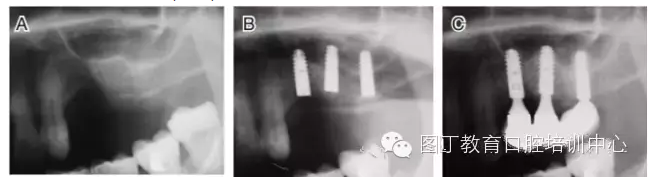

病例2 骨質(zhì)較少(圖4)

圖4